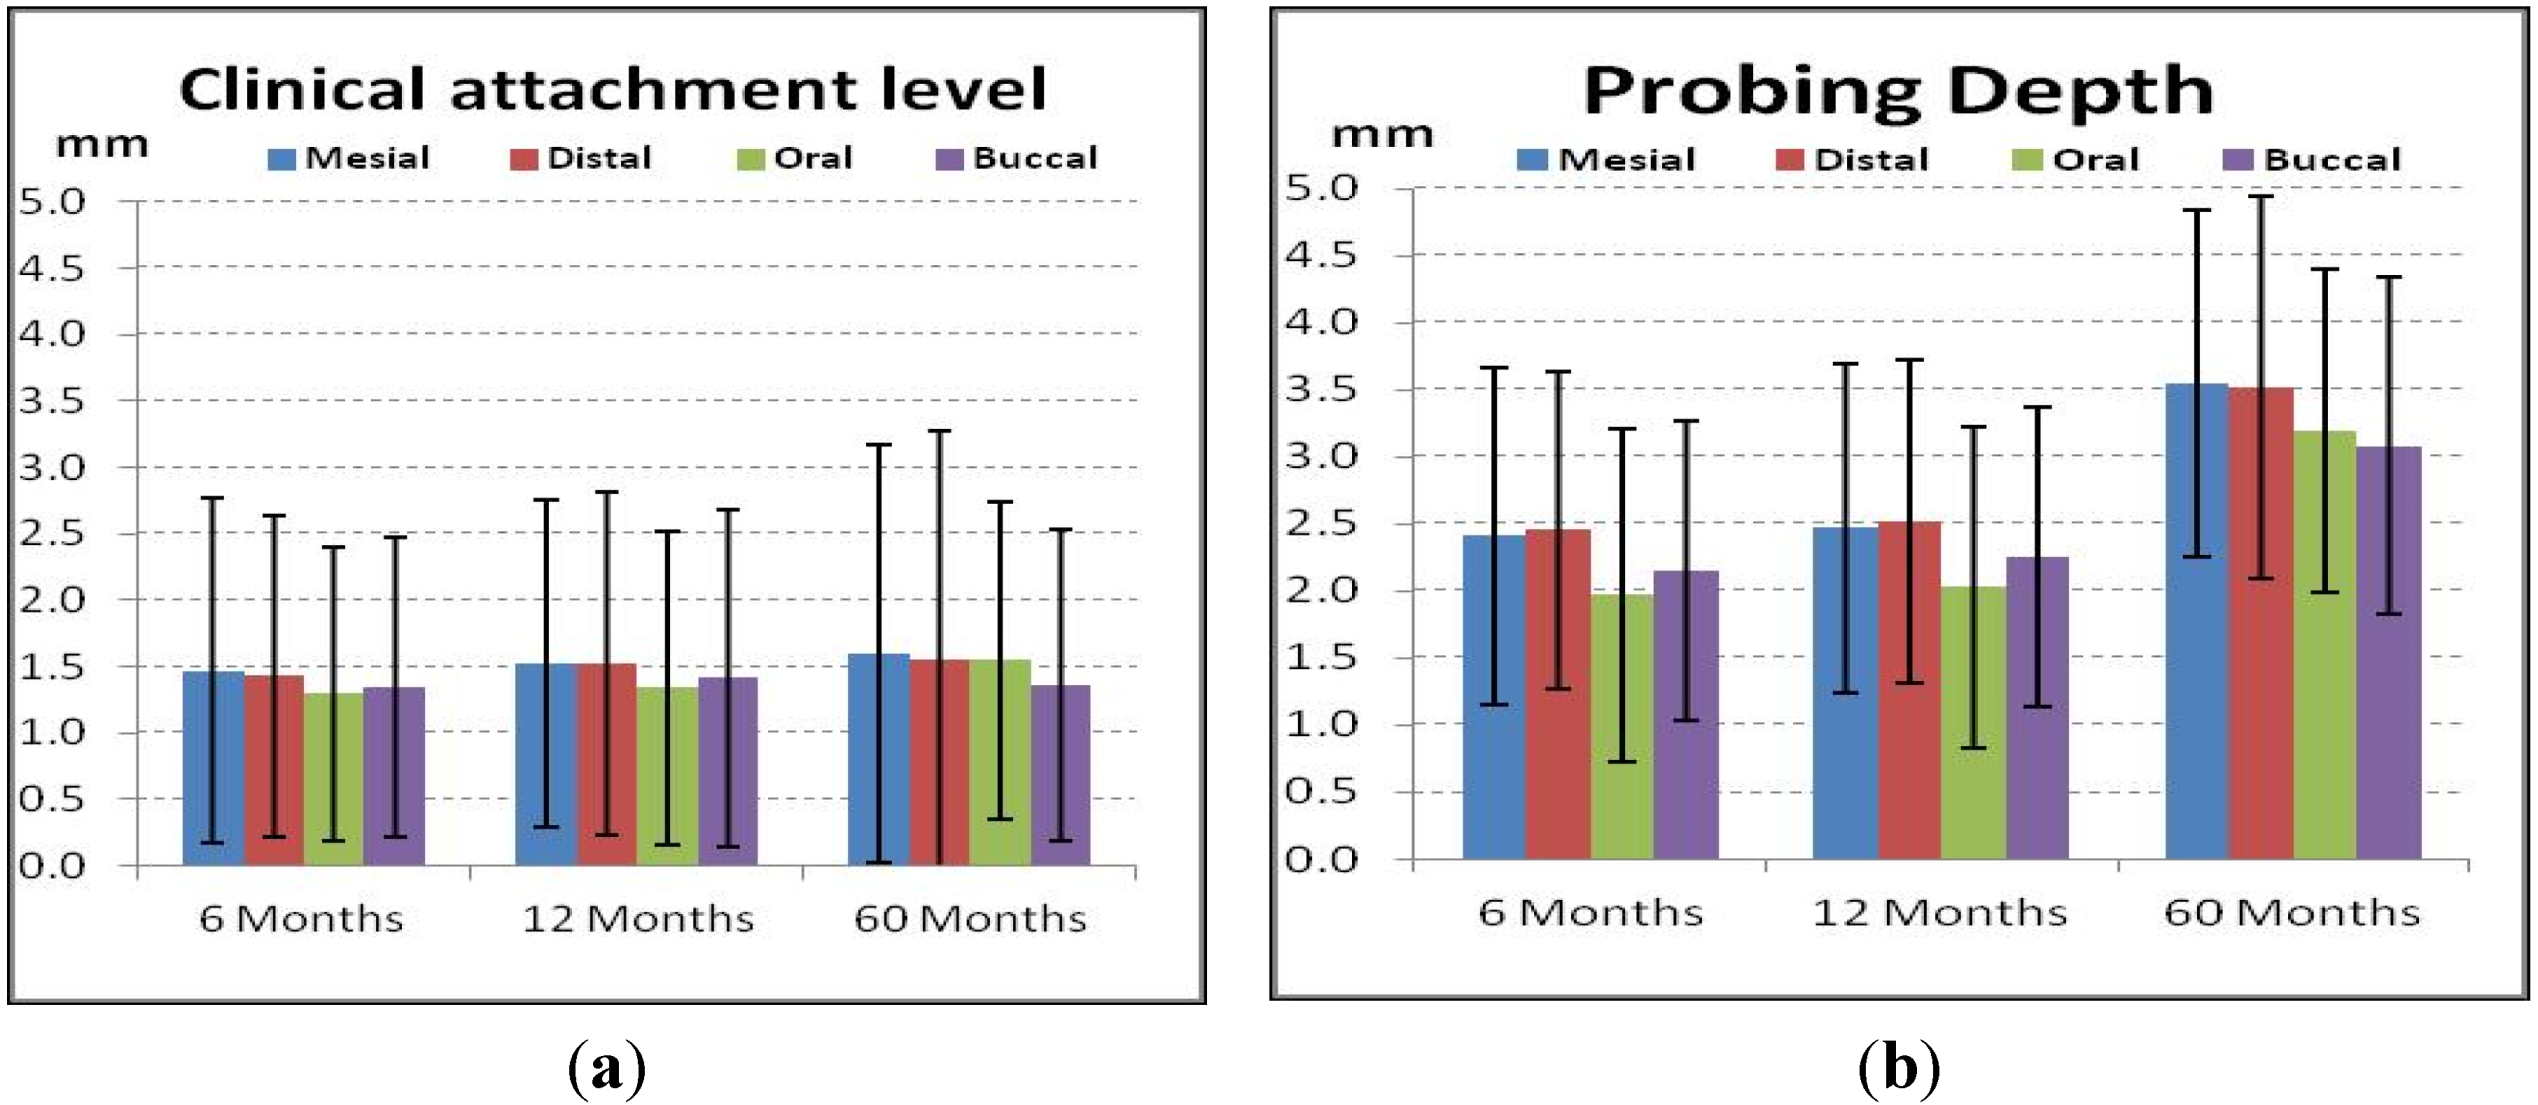

4.4. Periodontal and Radiologic Parameters